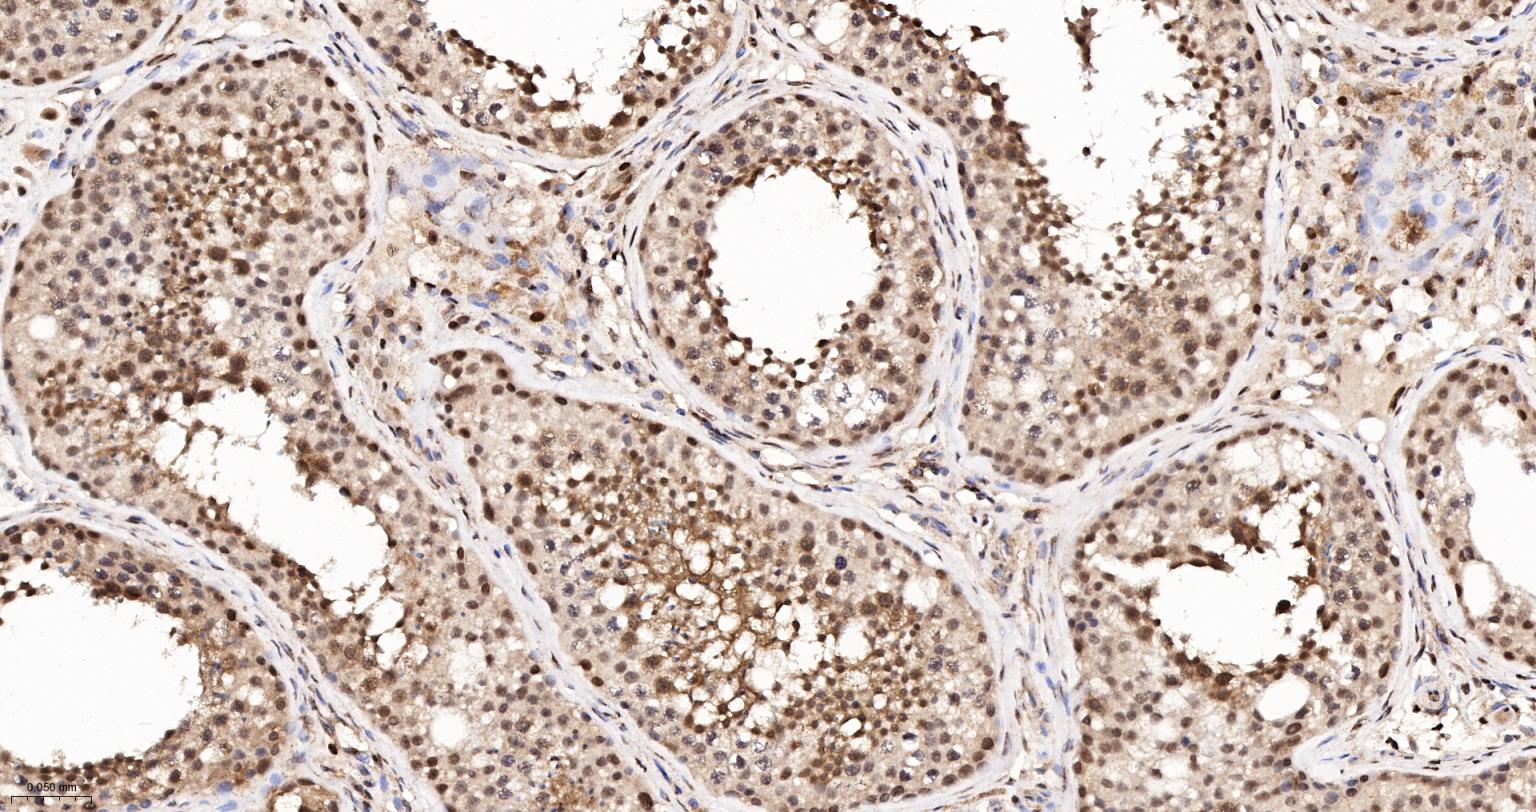

Paraformaldehyde-fixed, paraffin embedded Human Testicles; Antigen retrieval by boiling in sodium citrate buffer (pH6.0) for 15 min; The section was incubated with APEX1 Monoclonal Antibody, Unconjugated (bsm-60707R) at 1:200 overnight at 4°C, followed by conjugation to the bs-0295G-HRP and DAB (C-0010) staining.